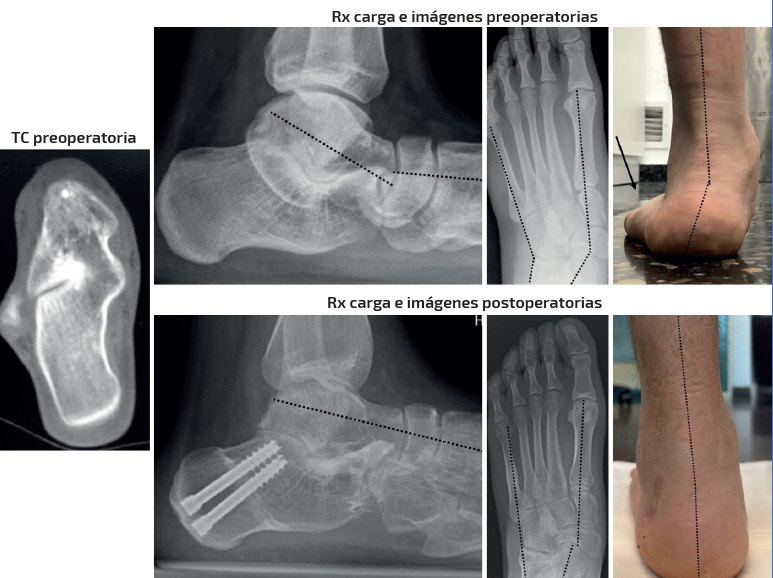

Caso 4 (Figura 7)

Se trata de una paciente mujer de 16 años. Afecta de coalición talocalcánea ósea con deformidad en valgo y abducto con subtalar rígida. Dolor medial y en sinus tarsi. Tipo IIB de Myerson. Tratamiento: osteotomía de alargamiento de la columna externa en el calcáneo y osteotomía pronadora según Cotton + alargamiento del tríceps sural según Strayer. Aloinjerto liofilizado de cresta. Seguimiento: 6 meses. Mejoría de la alineación clínica y del dolor preoperatorio. Mejoría de la alineación radiológica axial y dorsoplantar. Parámetros sagitales no valorables por no disponer de radiografía en carga lateral actual.